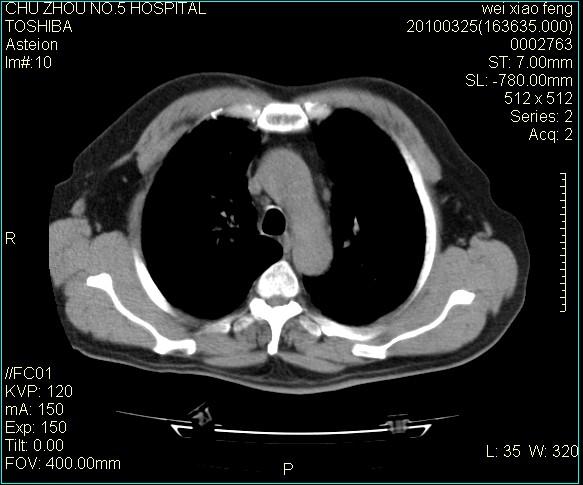

男,60岁,反复咳、痰、喘3月,加重3天。

间质性肺炎伴间质纤维化!不排除伴有职业病!

双肺间质纤维化,双肺血型潘散肺结核。

考虑间质性肺炎伴间质纤维化。

间质病变,间质炎症,间质纤维化趋势